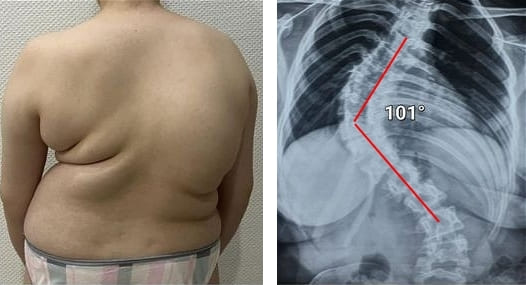

Veja esta radiografia. É a coluna vertebral de um homem de 44 anos, mas parece... a de um idoso. Antigamente, este tipo de lesão manifestava-se mais tarde, a partir dos 60 anos, mas hoje em dia é muito comum em pessoas com cerca de 40 anos. Estas alterações progridem com a idade e ignorá-las pode levar à perda total da mobilidade.

Coluna vertebral de um paciente de 44 anos: tudo começou com uma simples dor, mas numa semana surgiu uma hérnia e, em duas semanas, um deslocamento das vértebras, compressão do nervo e necessidade de cadeira de rodas.